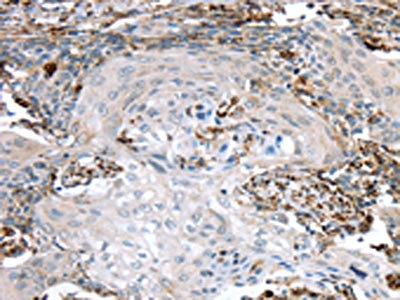

The image on the left is immunohistochemistry of paraffin-embedded Human cervical cancer tissue using CSB-PA550037(TBXA2R Antibody) at dilution 1/40, on the right is treated with synthetic peptide. (Original magnification: ×200)